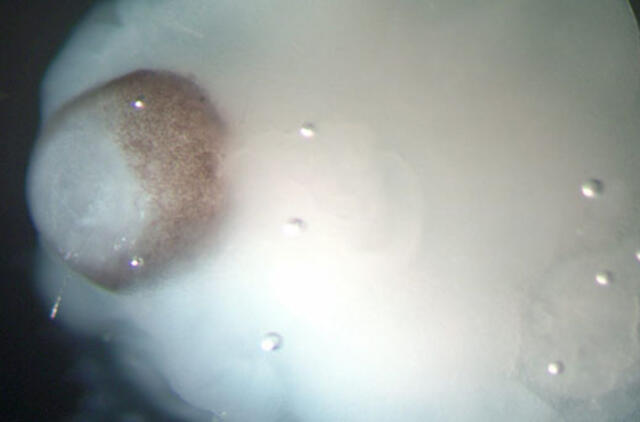

Žirnelio dydžio struktūra pasiekė tokį patį vystymosi etapą kaip devynių savaičių embrionas.

Mokslininkai įsitikinę, kad tai glaudžiai, bet netobulai, atitinka embriono smegenų vystymąsi iki devintosios savaitės stadijos.

Po dviejų mėnesių audiniai pasiekė maksimalų dydį - apie 4 milimetrus.